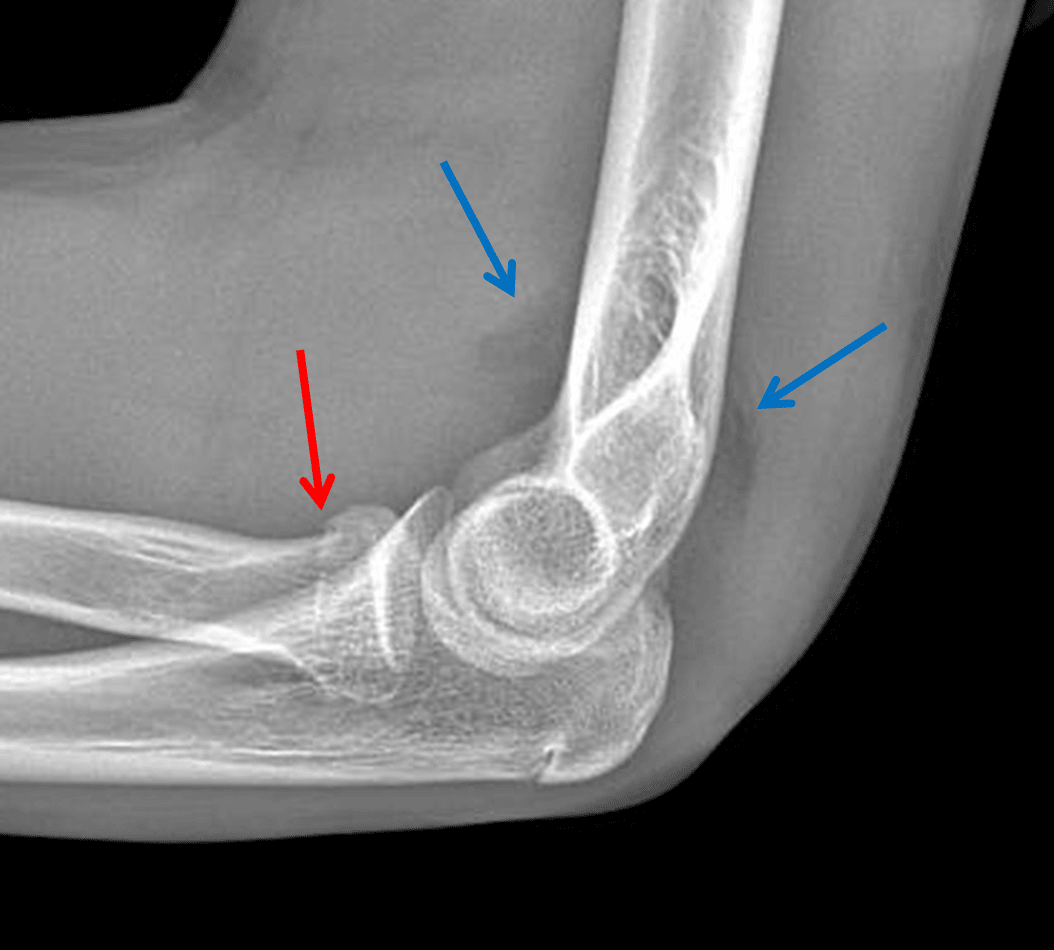

Radial head fracture

Acute mildly impacted radial head fracture.

Elbow joint effusion.

Red arrow: mildly impacted radial head fracture. Blue arrows: uplifted anterior and posterior fat pads indicative of a joint effusion.